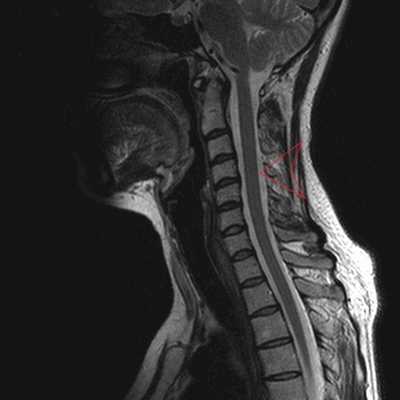

МРТ позвоночника в шейном отделе, оценка высоты дисков (указана красными линиями)

МРТ шеи: оценка спинного мозга (сагиттальная плоскость, Т2 последовательность)

МРТ шейного отдела позвоночника: оценка лордоза, сагиттальная плоскость, Т2 последовательность